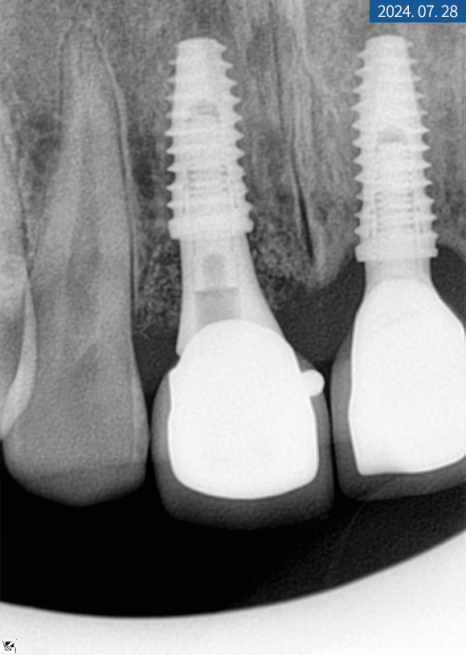

그렇게 3개월 후 아래턱 어금니는

교합과 인상 체득을 한 다음 쉐이드 가이드를 통해

크라운 색을 결정하고 보철물 제작에 들어갔답니다.

앞니는 차폐막을 걷고

커버 스크류를 뺀 후

힐링 지대주를 연결해 드렸는데요.

한 달 후 잇몸이 잘 아문 것을 확인하고

대구치와 동일하게

상부 보철물 제작에 들어갔습니다.

2주 후 기공소에서 받은

맞춤 크라운을 수복해 드렸으며

스크류도 단단히 조여서

풀리지 않게 고정해 드렸습니다.